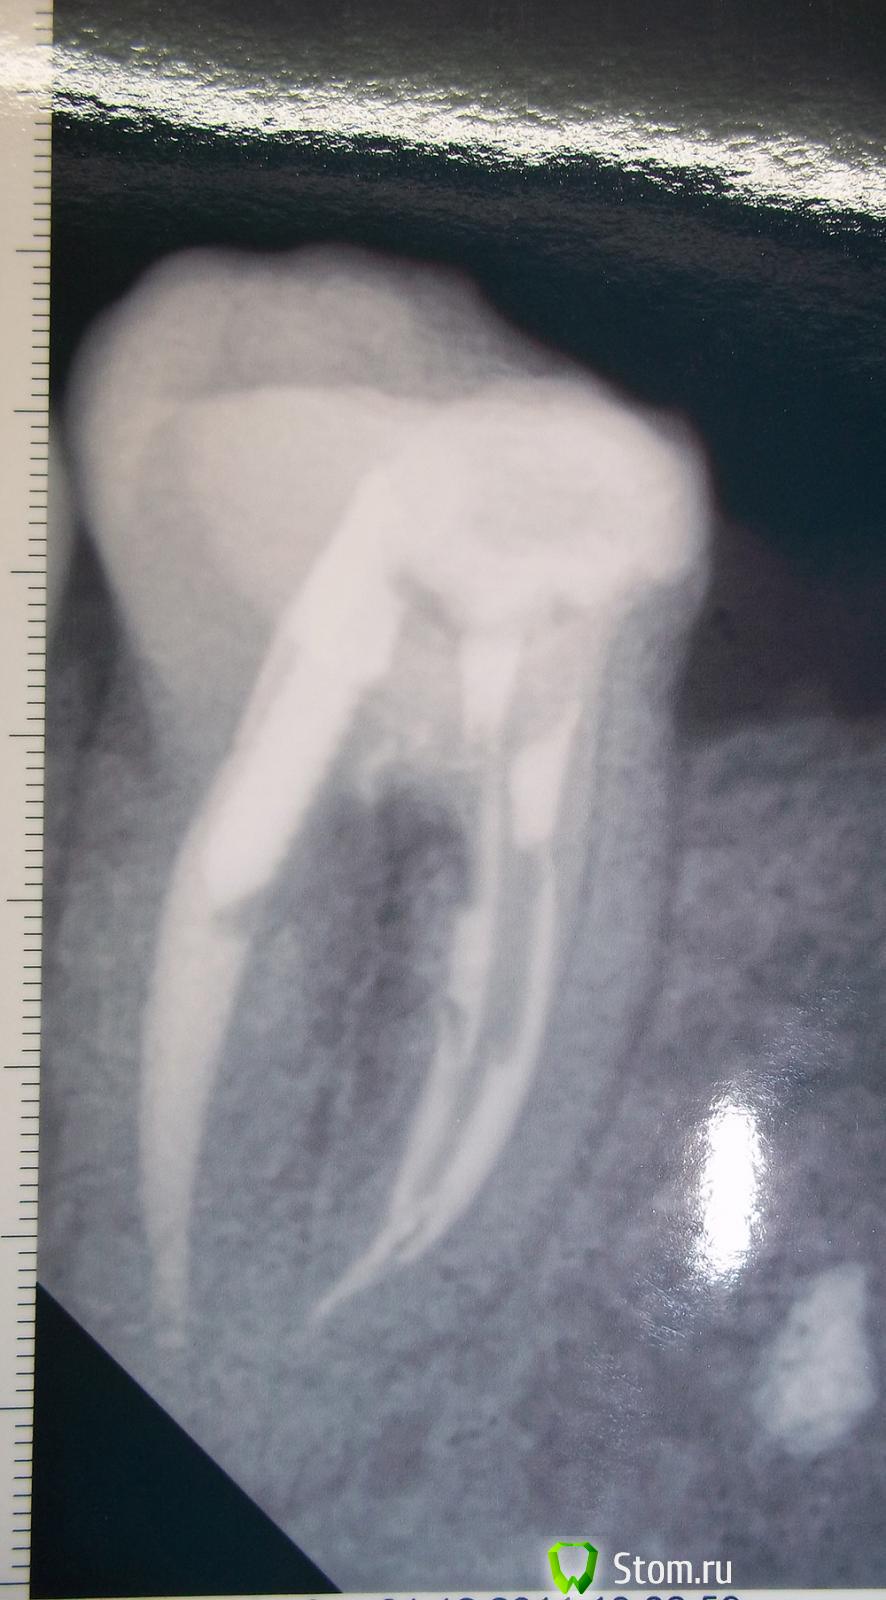

Satym Опубликовано 7 декабря, 2011 Поделиться Опубликовано 7 декабря, 2011 Здравствуйте. Подскажите, пожалуйста, мне. После лечения (нижней 6-ки) зуб заболел где-то через пол года. Врач снимок не делал, сказал, что не надо. Но, выяснилось, что канал не забит до конца. Это видно по снимку 1.jpg. Распломбировали этот не забитый канал, потом час, наверное, а может и больше в ручную иголкой "просверливали" этот канал, чтобы была возможность забить до конца. Положили какое-то лекарство. На следующий день распухла десна. Через неделю (точно не помню) пришла на повторный прием, положили лекарство с кальцием. Прошло полтора месяца, зуб болит, опухоль не спала. Врач сказал, что это лекарство не меняют. Надо ждать когда зуб заживет через несколько месяцев. На рисунке 2.jpg состояние зуба сейчас. Спасибо, Мария Ссылка на комментарий